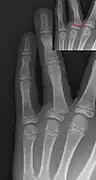

Salter–Harris II fracture of ring finger proximal phalanx.